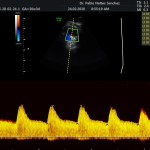

- La vitalidad y el bienestar fetal (Doppler).

- El Doppler de las arterias uterinas maternas y determinación de riesgo para pre eclampsia severa.